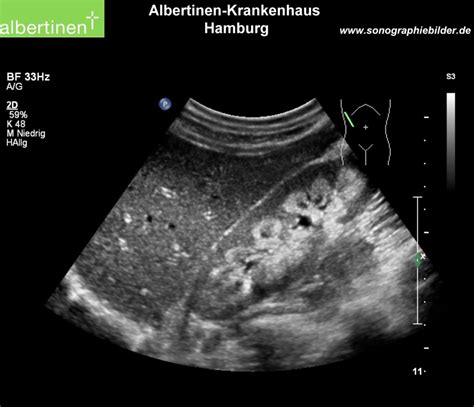

Interpreting the results of a Medullary Sponge Kidney USG requires expertise in radiology. The key findings that indicate Medullary Sponge Kidney include:

• Cystic dilatation of the collecting ducts in the renal medulla.

• Enlarged kidneys with a spongy appearance.

• Presence of kidney stones or calcifications.

• Thickening of the renal parenchyma.

These findings help in confirming the diagnosis of Medullary Sponge Kidney and guiding further management strategies.